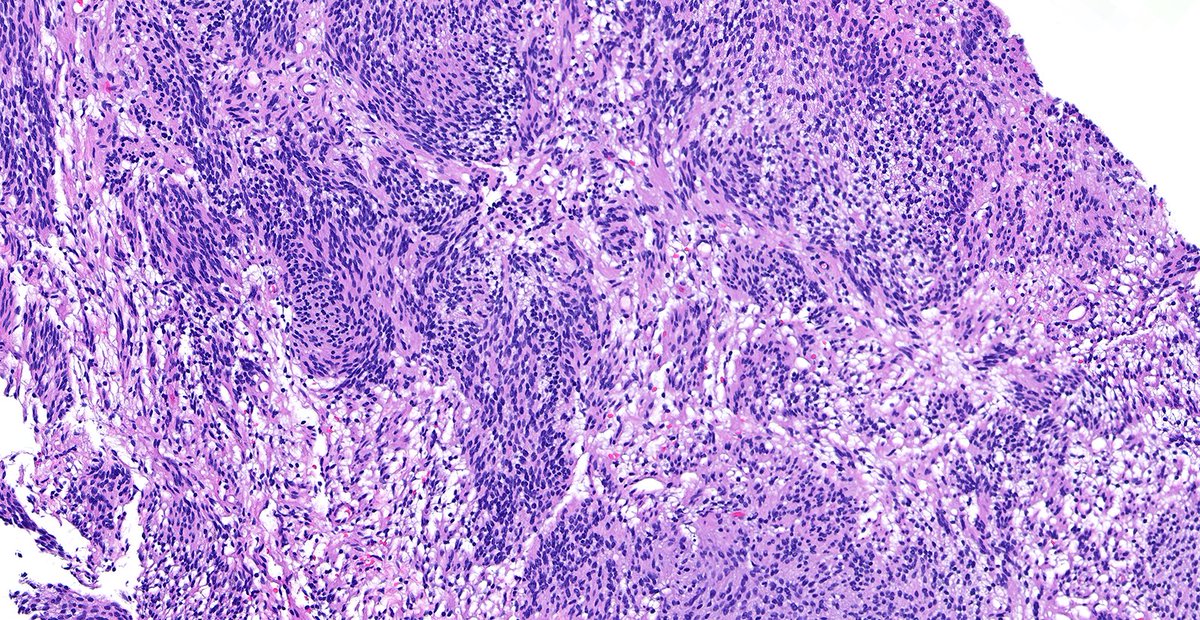

Not your average architectural distortion! Ductal carcinoma in situ can present this way, though more commonly with calcifications. thepathprincess.substack.com/p/ductal-carci… A reminder that classic presentations aren't the only ones!💡 #pathology #pathologist #breastpath #pathtwitter #pathX

Not your average architectural distortion! Ductal carcinoma in situ can present this way, though more commonly with calcifications.

thepathprincess.substack.com/p/ductal-carci…

A reminder that classic presentations aren't the only ones!💡

#pathology #pathologist #breastpath #pathtwitter #pathX